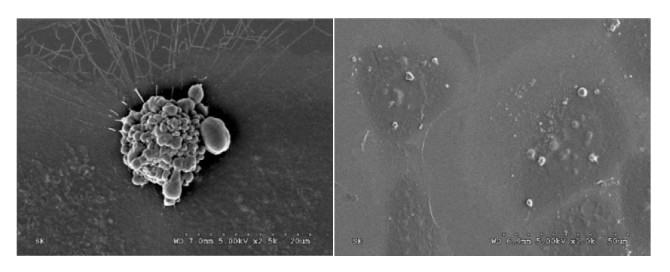

Izquierda: Célula renal humana en proceso de apoptosis inducido por cisplatino. Derecha: Células renales fagocitando cuerpos apoptóticos. Imágenes tomadas mediante microscopía electrónica de barrido. (Foto: UAM-UAH)

En la muerte por apoptosis las células se fragmentan en vesículas, denominadas cuerpos apoptóticos (CAs), que son eliminados por células con capacidad para ingerirlos. Un trabajo reciente, llevado a cabo por biólogos de la Universidad Autónoma de Madrid (UAM) y la Universidad de Alcalá (UAH) (España), ha demostrado que los CAs no son meros desechos celulares, sino que portan mensajes capaces de inducir la proliferación o la muerte de la célula que los ingiere.

Los CAs contienen en su interior componentes de la célula de origen, como porciones de citoplasma, orgánulos y, en algunas ocasiones, fragmentos nucleares agrupados de ma-nera aleatoria. Tradicionalmente no se ha atribuido a los CAs ninguna función fisiológica, salvo facilitar su ingestión (fagocitosis) y posterior degradación por células vecinas. Pero en los últimos años han aparecido evidencias que sugieren que los CAs podrían producir respuestas en las células que los fagocitan.